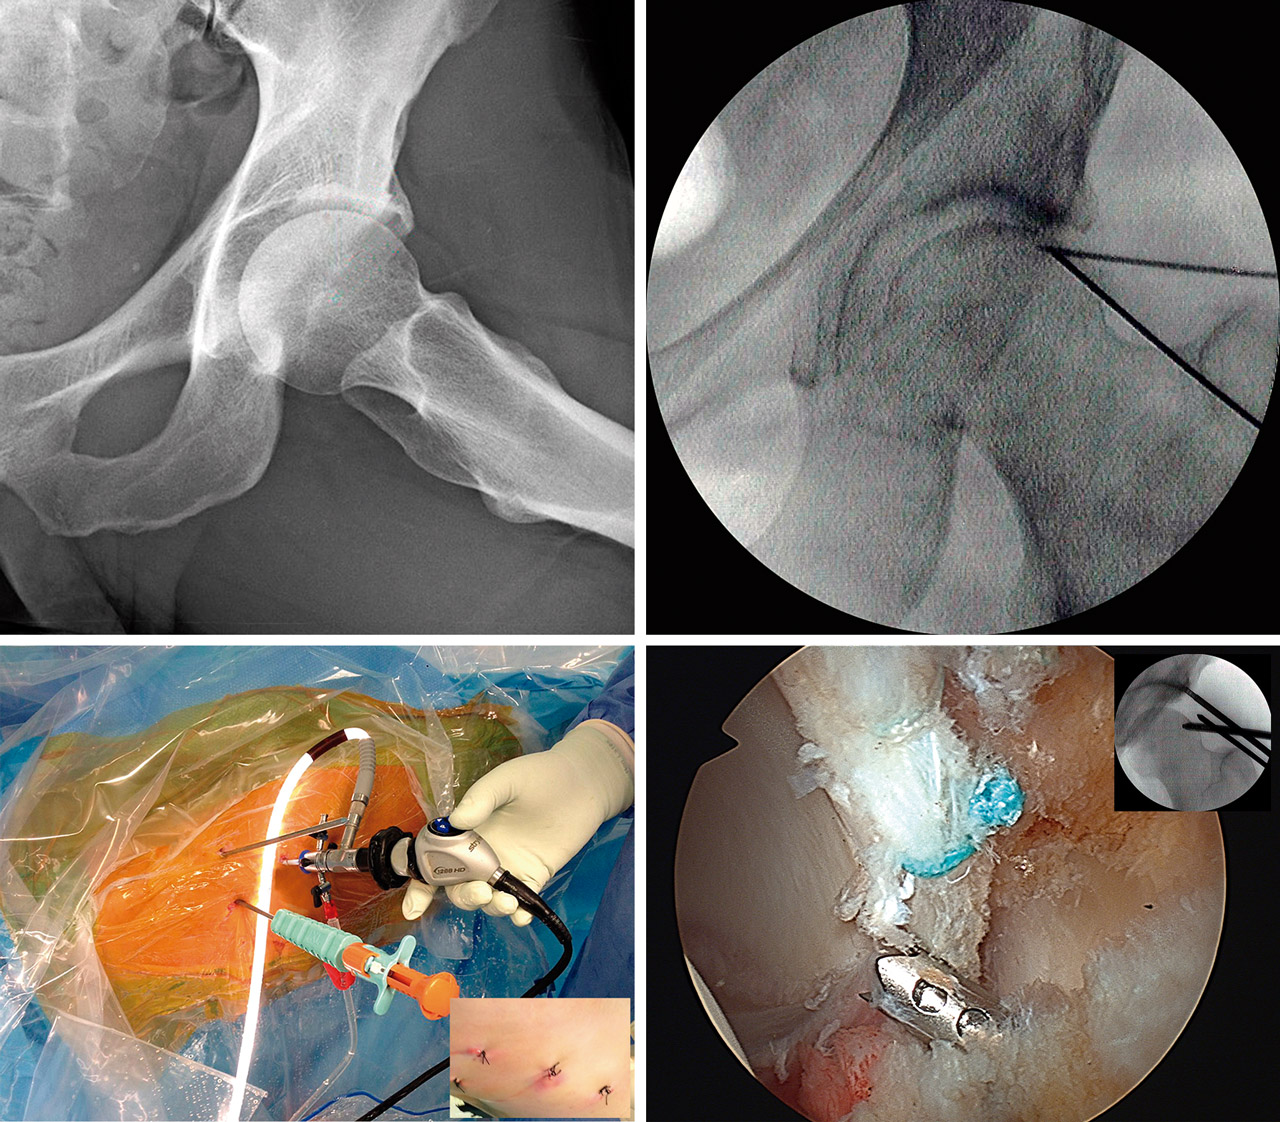

Como hemos señalado, realizamos el abordaje de la articulación desde el espacio precapsular, abordando en primer lugar el compartimento periférico según la técnica de “fuera-dentro” descrita por Horisberger(7)(8), popularizada en nuestro entorno por Margalet(12). Iniciamos la artroscopia con la óptica de 30° a través de un portal anterolateral (PAL). Dicho portal es análogo, en su ubicación, al de la técnica “dentro-fuera” descrita por Byrd en posición supina(5). Únicamente se aleja 4 cm del borde anterior del trocánter en dirección a la línea media del muslo de forma análoga a la técnica de abordaje desde el compartimento periférico, descrita por Dienst también sin tracción y en DS(6). Se permite así una oblicuidad de unos 10° de arriba hacia abajo que facilita el abordaje del espacio precapsular (Vídeo).

Aunque la técnica se puede realizar solamente mediante 2 portales(4), preferimos emplear 2 portales auxiliares de trabajo (3 en total), uno anteromedial más proximal (PAMP) y otro anteromedial distal (PAMD), similar al anteromedial modificado descrito por Matsuda(4), pero realizado bajo visión directa. El primero de estos 2 portales se establece bajo control radioscópico y permite realizar el desbridamiento del espacio precapsular, la capsulotomía, la desinserción lateromedial del LIF y la resección del PINCER en la zona anterior y superior (Vídeo).

El segundo portal auxiliar (PAMD) lo practicamos, como hemos señalado, bajo la visión intraarticular de la inserción de un catéter de abordaje, de forma que, permitiendo una correcta triangulación, se consiga el mejor ángulo y posición para la inserción de los anclajes, completar la acetabuloplastia en la zona posterior y, finalmente, suturar la cápsula de los casos indicados(13)(14).

Podremos así alcanzar hasta el punto horario de las 5:00 (7:00 en caderas izquierdas) sin añadir lesión capsular. Realizamos la reinserción del labrum desde el punto más proximal al más distal de su lesión (Figura 1 y Vídeo).

Para llevar a cabo la resección de las formas con exceso de cobertura, seguimos los conceptos de planificación propuestos por Matsuda(15). Así, dibujamos sobre la pantalla del intensificador el patrón de la zona de resección en la proyección anteroposterior (AP), como propugna Matsuda(15), pero también lo hacemos en la axial. Ello nos permite definir mejor la resección anteromedial y la superolateral. Iniciamos la resección de la zona superior y anterior de más fácil acceso, lo que además nos permitirá ir ampliando la resección. Dirigimos esta primero hacia la zona más anterior y medial, y después a la más lateral y posterior. Nos guiaremos en nuestra resección secuencial por las marcas realizadas sobre el intensificador hasta comprobar la normalización del ángulo de cobertura (zona superolateral) y conseguir la neutralización del signo de la pared posterior. Artroscópicamente, comprobamos la desaparición de los signos dinámicos de choque. La resección media realizada en estos casos es de unos 10 mm, como se ha publicado(15). Durante toda esta parte del procedimiento, mantendremos una tracción mínima, siendo suficiente evitar lesionar el cartílago de la cabeza femoral durante la acetabuloplastia de resección del PINCER. Una vez completada, aumentaremos la tracción e iniciaremos el tratamiento de las demás lesiones. En la Figura 2 podemos apreciar el resultado postoperatorio en relación con la valoración preoperatoria de este tipo de casos.

El objetivo será siempre preservar su integridad y función. No practicamos desinserción en ningún caso del labrum intacto ni siquiera para facilitar la exposición del PINCER(16). Realizamos la resección preservando y descubriendo la lámina condral en lo que se denomina efecto de “labralización”(15). Posteriormente, aunque no esté desprendido, suele ser necesario proceder a su refijación al nuevo borde acetabular según la técnica habitual con anclajes. Realizamos en primer lugar la fijación a las 12:00; ello nos permite levantar el labrum “caído” facilitando la maniobrabilidad del instrumental en el CC. Para ello, como se muestra en el Vídeo, empleamos actualmente anclajes de los denominados “todo hilo”: bien el modelo SutureFix Ultra® de 1,7 mm y sutura UltraBraid® de #2 (Smith & Nephew Inc., Andover, MA, USA), bien el modelo Q-Fix® de 1,8 mm e igualmente con sutura de #2 (Smith & Nephew Inc., Andover, MA, USA).

Las directamente relacionadas con la lesión PINCER, por su carácter frecuentemente periférico, suelen ser completamente resecadas por efecto de la acetabuloplastia de resección. En algunas ocasiones, podemos encontrar lesiones más extensas producto de la frecuente asociación a lesiones de tipo CAM. En estos casos, optamos por realizar técnicas de tipo AMIC (autologous matrix induced chondrogenesis)(17)(18), que asocia bien una membrana de colágeno de tipo Chondro-Gide® (Geistlich Pharma AG, Wolhusen, Switzeland) a la conocida técnica de microfracturas en lesiones mayores de 2 cm de diámetro(19), o bien una matriz de tipo líquido como el BST-CarGel® o Chitosan (Smith & Nephew Inc., Andover, MA, USA)(20), que empleamos en lesiones de menor tamaño(21).